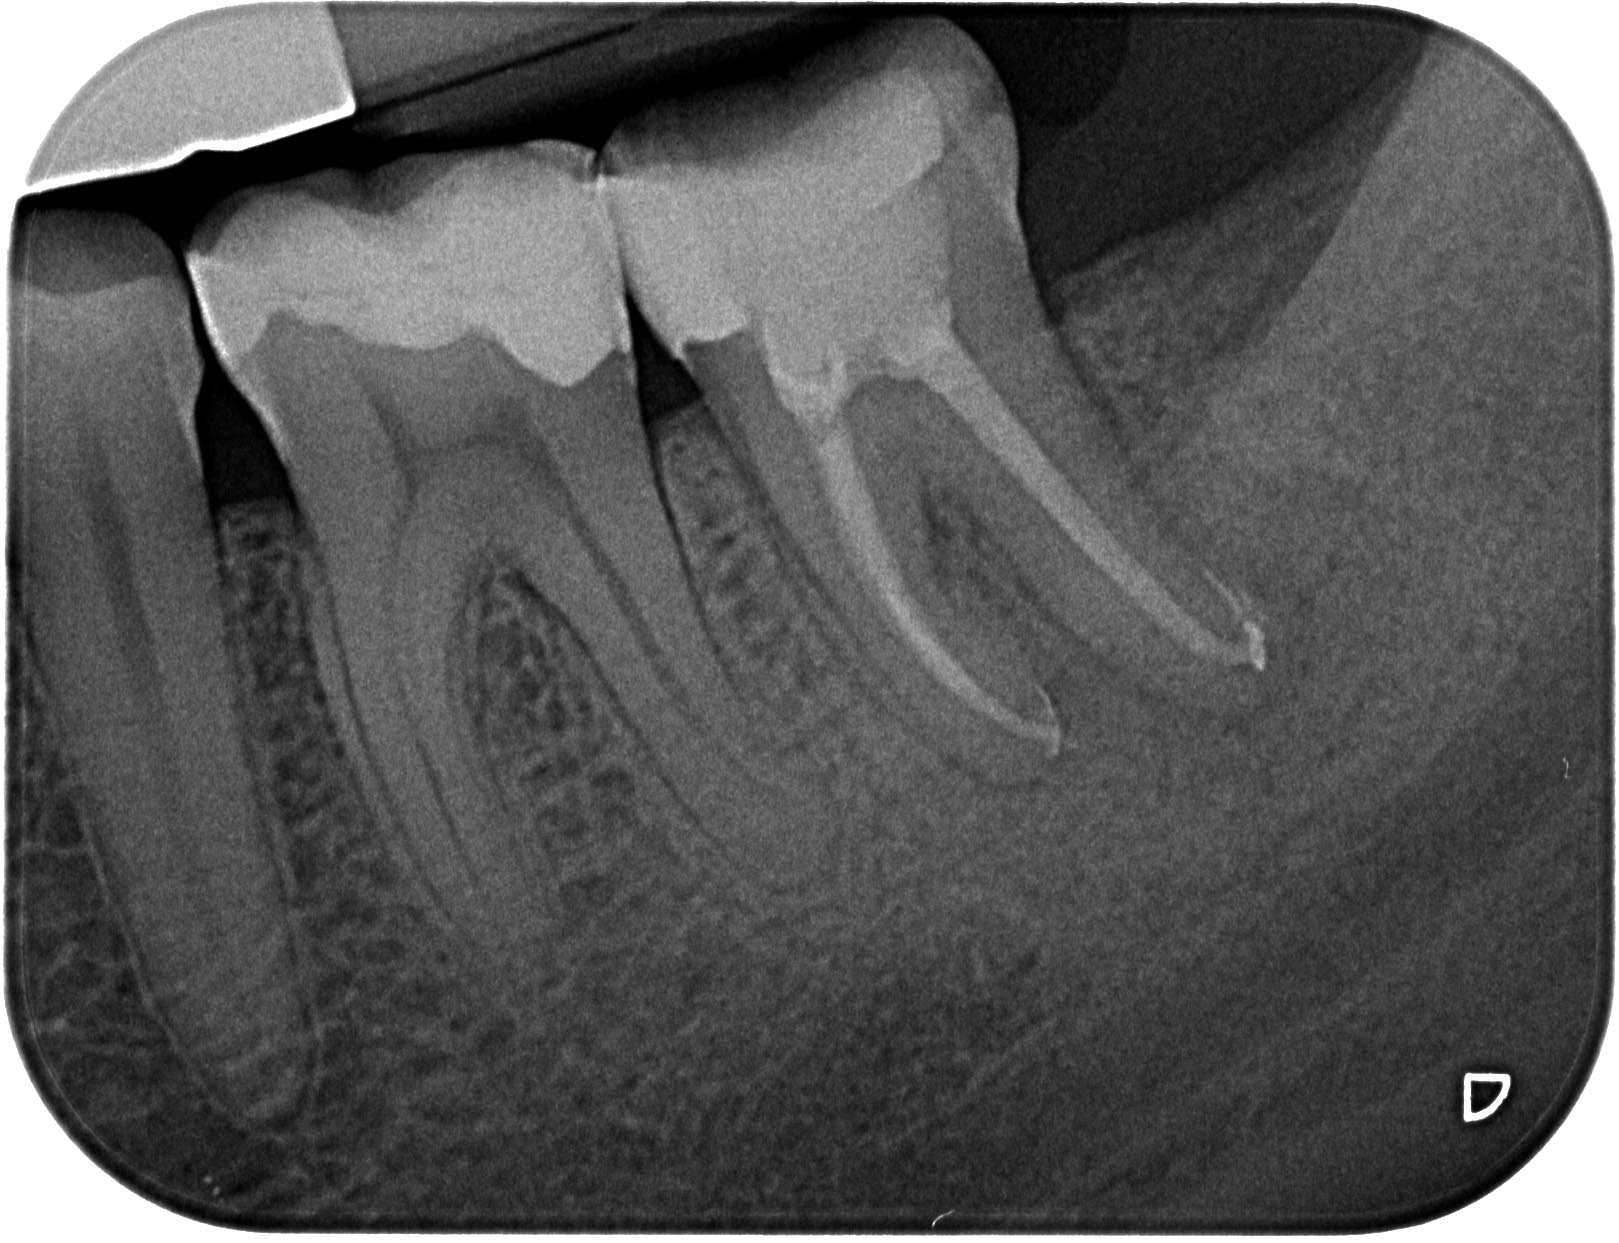

AA-1-3 Veröffentlicht 11. September 2012 am 1619 × 1243 in Recall des Tages – Zahn 37 mit apikaler Aufhellung